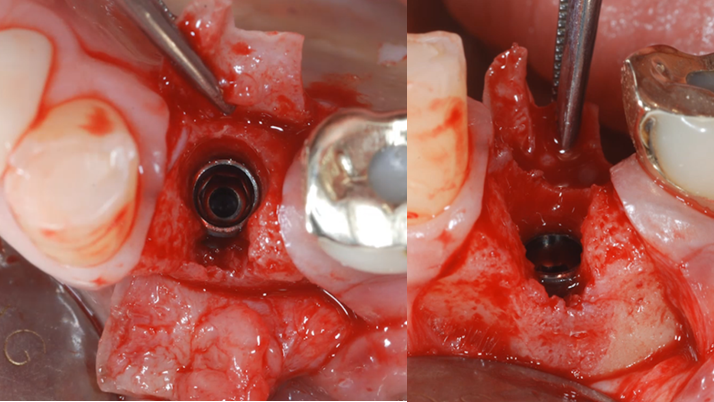

Clinical case: : Immediate loading of lower molars using R2Gate prefabricated 3D-printed provisional restoration

- Courtesy of Dr. Sam Omar, Egypt -

Keywords

Dr.Sam Omar, immediate loading, digital guided surgery, digital ONE-DAY implant, maxillary anterior, #21, guided surgery, immediate loading, AnyRidge, R2GATE, Mega ISQ, MEG Torq, R2GATE Full Surgical Kit

Products:

implant system, R2GATE Guide, R2GATE surgical kit (AnyRidge), Mega ISQ

“ONE-DAY implant, one-day smile

”